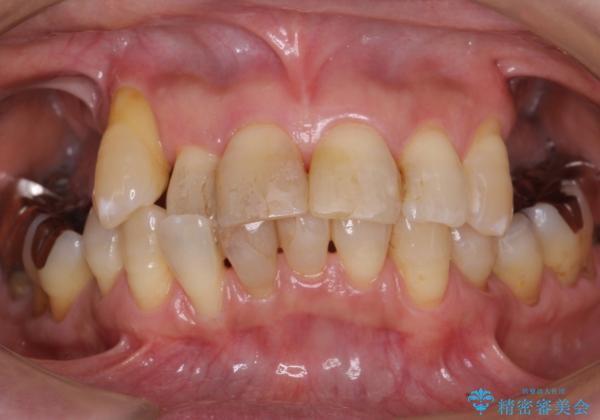

- 上の奥歯がないまま長年過ごしていたら前歯もぐらぐらしてきてしまったことを主訴に来院された患者様です。

奥歯の咬み合わせがないことにより前歯に負担がかかり動揺が出ていました。

上の前歯は動揺を抑え、入れ歯の着脱にも耐えうるように被せ物を連結させることにしました。

しっかりと咬むことができるようになり喜んで頂けました。

全体的な歯の動揺もなくなり安心して頂けました。

4年経過しましたが問題なく調子が良いとおっしゃって下さいました。